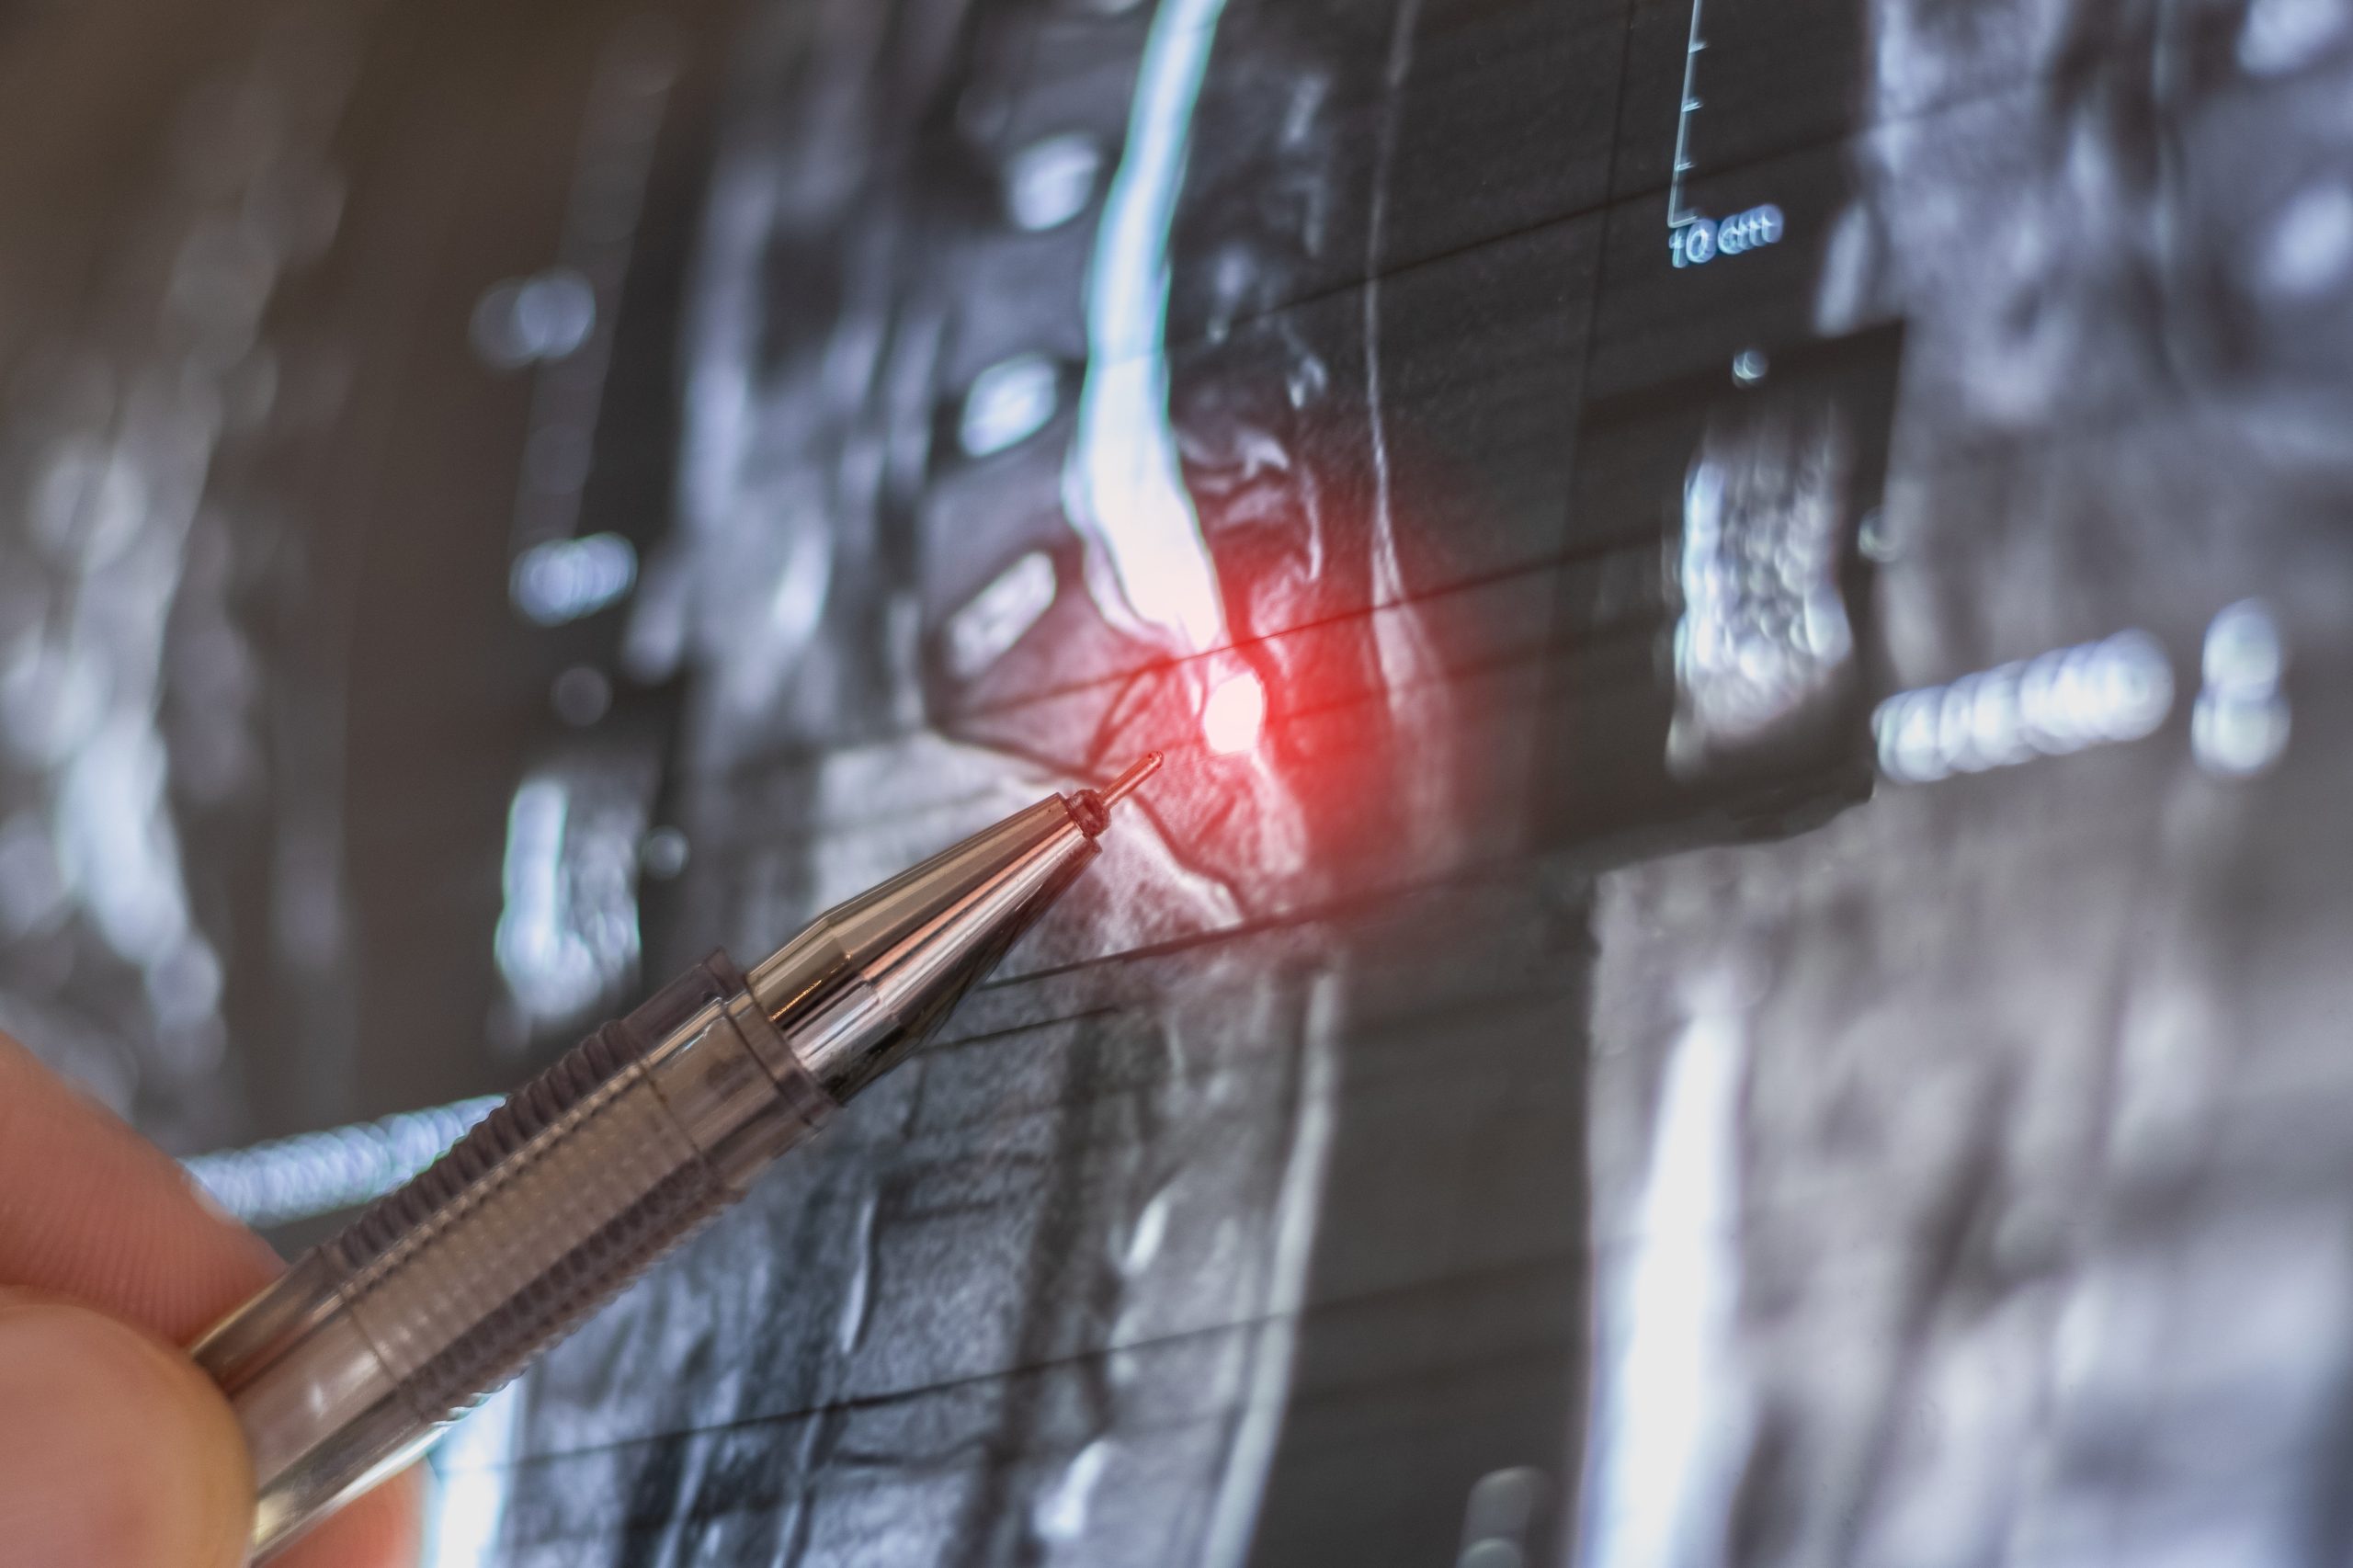

Pain Conditions We Commonly Manage

Back Pain

Back pain may affect movement, posture, work, and daily activity. Some cases are short-term, while others may recur or persist over time.

Neck Pain

Neck pain may be associated with posture, muscle tension, degenerative changes, or other contributing factors.

2. Understanding Contributing Factors

Pain may be influenced by posture, movement, previous injury, degenerative changes, nerve-related issues, lifestyle factors, or underlying medical conditions.